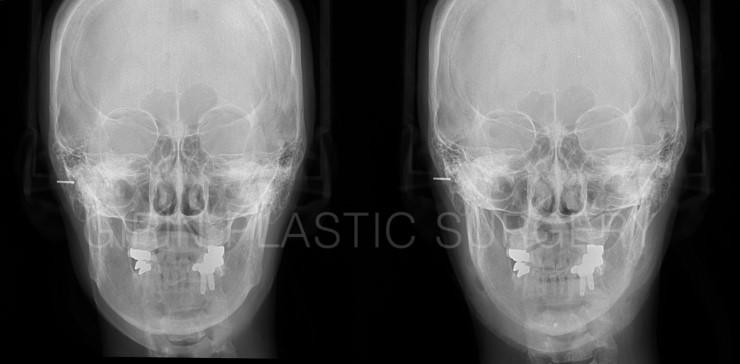

수술후6주차 정면

정면모습을 보면 긴곡선절제 시 앞턱중앙까지 절골했기 때문에 앞턱폭이 줄어든게 확인됩니다. 6주차로 아직 부기가 남아있어 6개월이상 꾸준히 좋아지는게 느껴질겁니다. 티절골을 한것과 같은 효과가 있지만 수술후 붓기 및 회복속도가 현저하게 차이나고 수술후예후도 다릅니다. 가장 심플한 예를 들자면 엑스레이상 드러나는 고정핀입니다. 티절골은 조각난 뼈를 모아준뒤 고정하는 핀이 엑스레이에 보이지만 긴곡선은 고정핀이 전혀 없습니다.

정면 엑스레이

엑스레이상 뼈가 깔끔하게 잘렸습니다. 수술후 엑스레이 및 시티는 수술다음날 퇴원할때 촬영하기 떄문에 연부조직이 조금 부은 모습입니다.

정면 CT

정면에서 보이는 귀밑각이 넓은편이 아니라 아래턱의 가로폭변화는 크지 않지만 앞턱모양은 많이 변화했습니다.